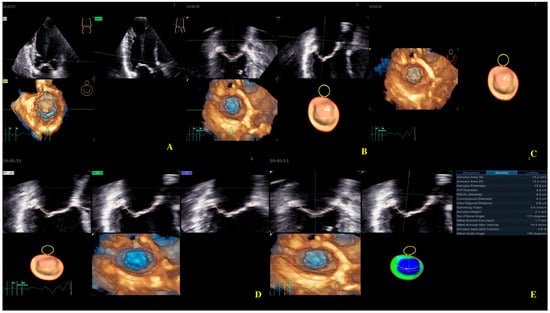

Four-dimensional echocardiography image acquisition of the MV for quantitative analysis is usually performed in the A4ch view on transthoracic echocardiography [23,24]. An optimal view was selected for the most MV favorable segmentation. The 4D Auto MVQ software package enabled the detection of anatomic landmarks (Figure 4), followed by surface modeling using a geometric mesh. Finally, we obtained the annular and leaflet geometry, as well as their dynamics (Figure 5) [25,26,27].

Figure 4.

Mitral valve segmentation and quantification (A), detection of mitral valve anatomic landmarks (B), mitral valve commissures pointing (C), mitral valve scallops pointing (D), mitral annulus parameters (E).

Figure 5.

Mitral annulus parameters provided by Four-Dimensional Auto Mitral Valve Quantification (4D Auto MVQ) software: (A) Final parameters values; (B) AA—annular area; (C) AP—annular perimeter; (D) AP diameter—anteroposterior diameter; (E) PM-AL diameter—posteromedial to anterolateral diameter; (F) CD—commissural distance; (G) Itd—intertrigonal distance; (H) AH—annular height; (I) NPA—nonplanar angle; (J) TH—tenting heigh; (K) TA—tenting area; (L) TV—tenting volume.